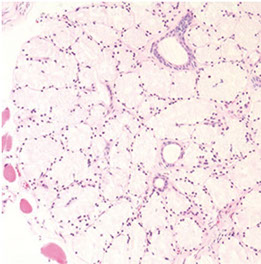

Benign prostate c corpora amylacea

Benign Prostatic Hyperplasia (BPH)

aka nodular hyperplasia, MC urologic dz in men

BPH